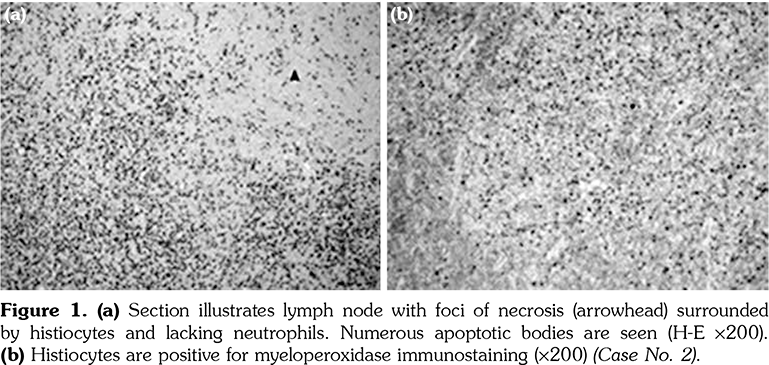

Diagnosis of KFD depends upon presence of appropriate histopathology of the lymph node (LN), which typically shows paracortical well-circumscribed necrotic lesions consisting of karyorrhexis, fibrin deposits, abundant CD68 plasmacytoid monocytes and infiltration of histiocytes in absence of plasma cells or neutrophils.[2-5]

The excised cervical LNs of the 11 patients showed variable degrees of necrotizing lymphadenitis with foci of necrosis surrounded by histiocytes that are positive for CD68 and myeloperoxidase. The histopathology of the excised LN for patients numbered 2, 3, and 7 is illustrated in Figures 1, 2 and 3, respectively.